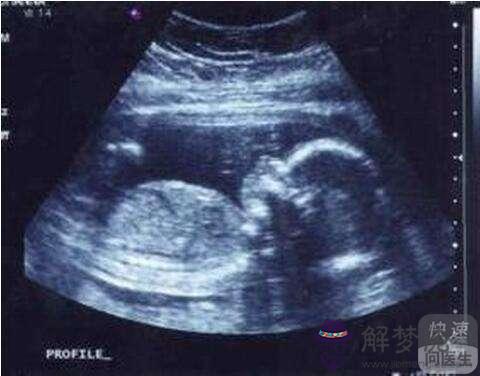

九、看B超孕囊數據。據說孕囊呈長條狀的是男孩,圓圓的是表示懷女孩。